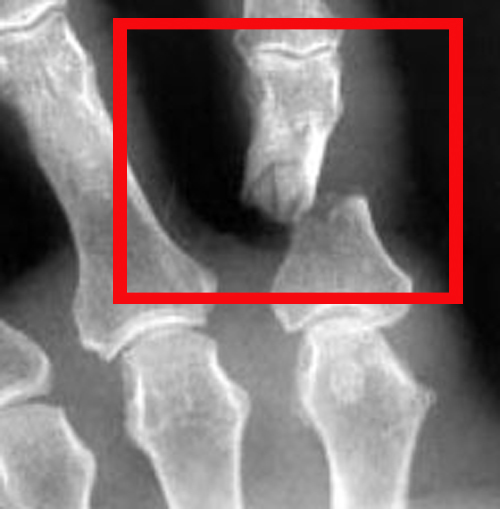

Снижение вывиха пальца должно выполняться только в медицинском учреждении квалифицированным специалистом. При необходимости перед процедурой может быть проведена рентгенография поврежденного сустава для точной оценки степени травмы.

Процедура вправления

Закрытые вывихи фаланг пальцев обрабатываются дезинфицирующим раствором и анестетиком для обезболивания, после чего проводится вправление.

В сложных случаях может быть введена тонкая спица с фиксацией в специальной дуге или используется цапка. Врач аккуратно вытягивает поврежденный палец, в то время как ассистент удерживает голень пациента, создавая необходимую противотягу. При достаточном натяжении хирург вправляет смещенную фалангу, оказывая давление в нужном направлении.

После процедуры проверяется подвижность сустава и выполняется контрольная рентгенография. Врач накладывает фиксирующую повязку из лейкопластыря или шину, соединяя пострадавший палец с соседним. Это позволяет пациенту сразу начать восстанавливать двигательную функцию конечности. Через 2–3 дня повязка дополнительно укрепляется лейкопластырем. При множественном вывихе, сопровождающемся переломом костей, применяется гипсовая фиксация на срок около 3 недель.